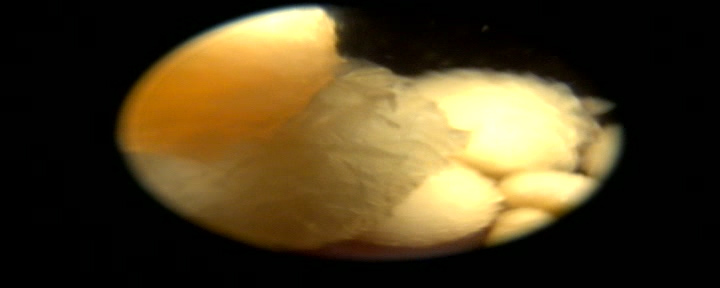

De behandeling viel voor onze dierenarts uiteindelijk wel wat tegen. Niet omdat het verwijderen van de blaasstenen via de scoop niet lukte, maar omdat er zo ontzettend veel blaassteentjes aanwezig bleken te zijn.

Het verwijderen van de blaassteentjes verliep soepel met behulp van allerlei grijpertjes.